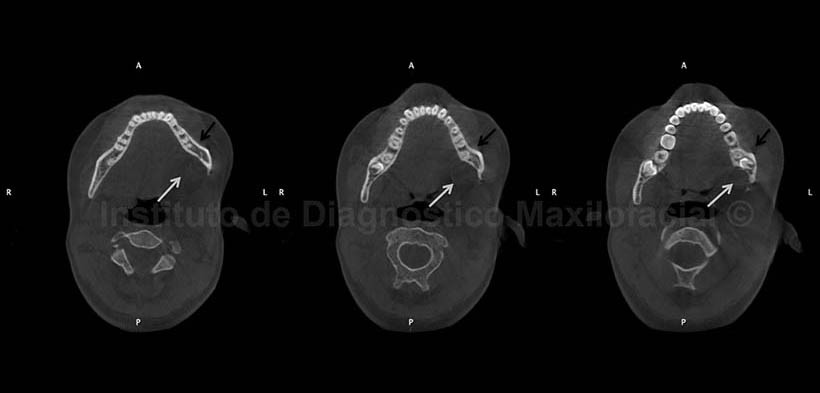

La tomografía computarizada cone beam (CBCT), en cortes axiales (Fig.2), muestra el socavamiento de la tabla ósea lingual a nivel del germen dentario de la pieza 3.8 (flechas blancas) y el remodelado óseo a nivel de la tabla vestibular (flechas negras), a consecuencia del efecto de masa a dicho nivel.